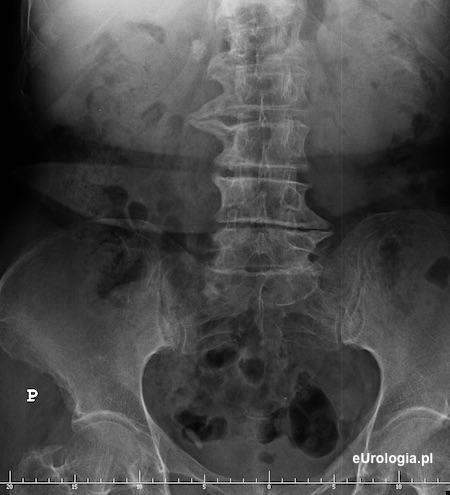

Zdjęcie przeglądowe nerek i pęcherza - cień wpaienny w miednicy po stronie prawej o wymiarach 20x10 mm

Kamień w dolnym odcinku prawego moczowodu - cień wapienny w miednicy małej widoczny na zdjęciu przeglądowym nerek i pęcherza.